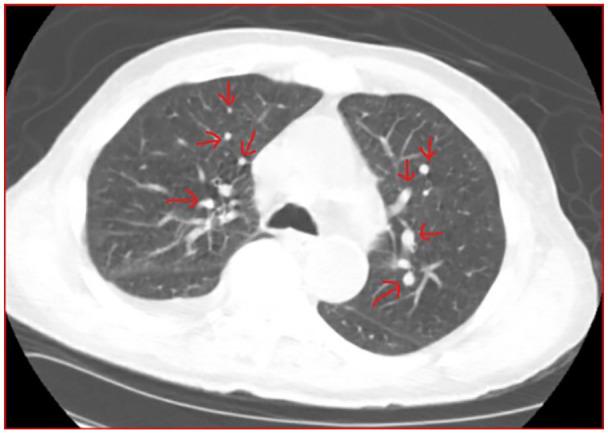

Among thoracic tumors, these include subsets of a relatively newly described and yet to be fully characterized tumor entity: SMARCA4-deficient Undifferentiated Tumor (SMARCA4-dUT). Mutations of SMARCA4 (SWI/SNF-related, matrix-associated, actin-dependent regulator of chromatin, subfamily A, member 4) gene and loss of BRG1 (Brahma-related gene-1) is the underlying molecular hallmark of SMARCA4-dUT. They mostly involved the mediastinum, lung, and/or pleura showing undifferentiated round cell or rhabdoid morphology associated with aggressive clinical behavior. The pathogenesis of these tumors is still not clear. Morphologically, SMARAC4-dUT is differentiated from SMARCA4-dNSCLC by the presence of squamous and solid components in the latter. Immunohistochemically SMARC4-dUT has characteristic loss of SMARCA4 and SMARCA2 and strong expression of SOX2, CD34, and SALL4. Common sites of metastasis include lymph nodes, bones, and adrenal glands but rarely brain metastasis. We present a unique and rare case of a 76-year-old male with a right lung mass with documented pathology of SMARCA4-dUT and was found to have multiple brain metastases.

在胸部肿瘤中,这些包括相对新近描述且尚未完全特征化的肿瘤实体的亚组:SMARCA4 缺陷型未分化肿瘤(SMARCA4-dUT)。SMARCA4(SWI/SNF 相关的、基质相关的、肌动蛋白依赖性染色质调节因子亚家族 A 成员 4)基因突变和 BRG1(Brahma 相关基因-1)的缺失是 SMARCA4-dUT 的潜在分子特征。它们主要涉及纵隔、肺和/或胸膜,表现为与侵袭性临床行为相关的未分化圆形细胞或横纹肌样形态。这些肿瘤的发病机制尚不清楚。在形态学上,SMARAC4-dUT 与 SMARCA4-dNSCLC 不同,后者存在鳞状和实性成分。免疫组织化学显示 SMARC4-dUT 具有特征性的 SMARCA4 和 SMARCA2 缺失以及 SOX2、CD34 和 SALL4 的强烈表达。常见的转移部位包括淋巴结、骨骼和肾上腺,但很少有脑转移。我们报告了一例 76 岁男性的右侧肺部肿块,其病理学证实为 SMARCA4-dUT,并发现有多个脑转移。